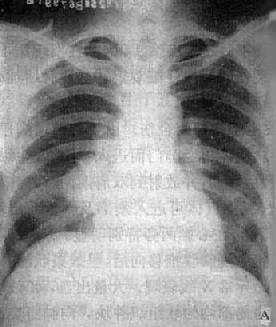

图3-1-28 右上叶支气管肺癌(中心型)

A.后前位B.前后位体层像右上叶密度均匀增高,下缘清楚、上突,

与肺门肿块影形成似横置S状。体层像示肿块突入右支气管腔内